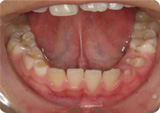

左は正常な舌小帯です。右は舌小帯の低位付着により舌の挙上が困難になっています。

重度なものでは発音や嚥下(飲み込む動作)に影響を及ぼします。